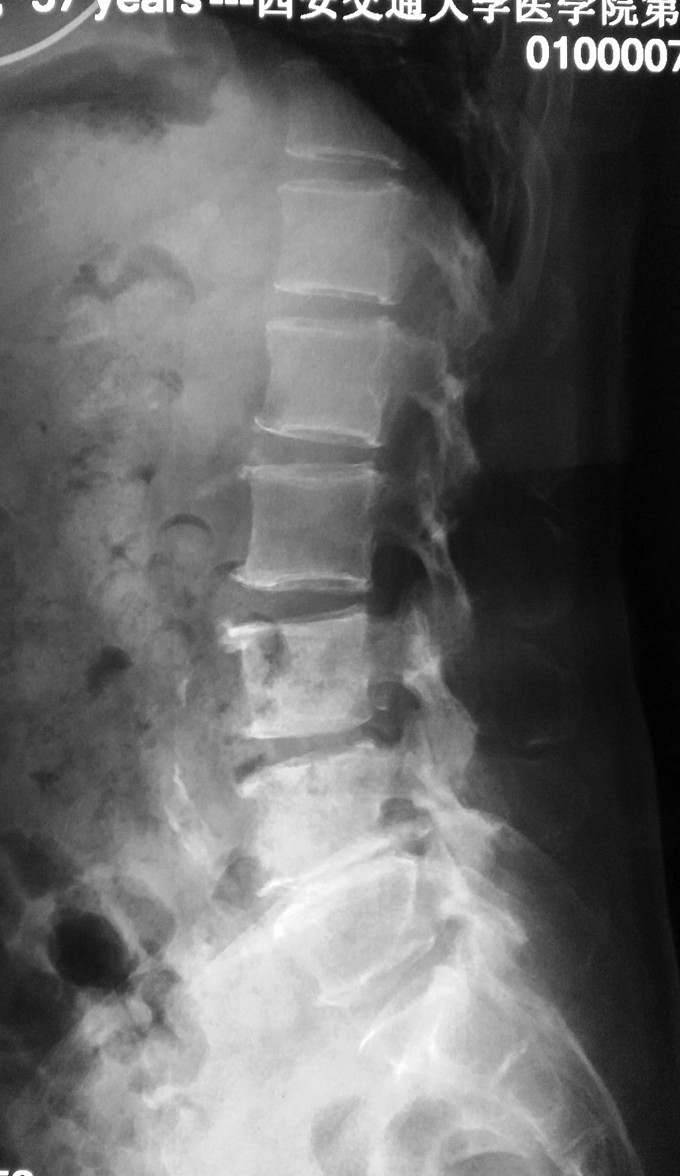

患者女性,58岁。 腰痛间断性发作2年,加重伴左下肢疼痛不适4月 疼痛以久坐和劳累后症状明显,近4月上述症状加重,伴有左下肢麻木疼痛感,经卧床休息后不能缓解。

腰3-4/4-5间隙及椎板压痛及叩击痛,无明显下肢放射痛。左大腿前外侧及膝以下感觉有减退,左侧髋、膝肌力5级,拇趾背伸肌力4级,肌张力不高,左下肢直腿抬高试验40°阳性,加强试验阳性。右下肢感觉肌力正常。 血沉 99mm/h C反应蛋白:4.1ng/L 斑点试验:抗A 111,kangB 127

1.腰3-4结核 2.腰4-5椎管狭窄 因术前血沉比较高,所以予以HREZS抗痨治疗2周,血沉至44mm/h,患者一般情况较前好转。安排手术治疗:后路腰3-4椎间病灶清除椎板植骨+腰4-5减压植骨内固定融合术。